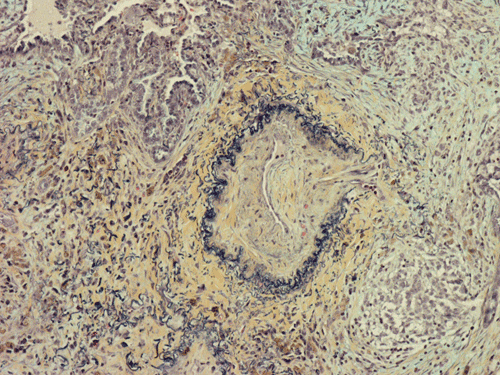

At scanning magnification (Panel A), the lung parenchyma is replaced by some coalescing fibrous nodules. The degree of involvement is variable at different fragments (Panel B and C). In the less affected areas, there are some fibrotic thickening of the septa (Panel C). In some areas, the changes are minimal and the pleural appear to be uninvolved (Panel D and E). In low to medium magnifications, these nodules of fibrosis contains a large number of hemosiderin laden macrophages (Panel F and G) admixed with fibrous tissue. The diagnostic tissue, however, is present in areas with increased cellularity. In these areas, there is a background of cells with a moderate amount of cytoplasm and bland nuclei. Some of these nuclei have kidney shape (arrow in Panel H). In some areas, many of the nuclei have a deep nuclear groove that resemble a coffee bean (arrow in Panel I). In the third type of areas, the nuclear grooving is not distinct (Panel J). Prominent eosinophilic infiltrations are almost always present. Immunohistochemistry on CD1a revealed many positive cells (Panel L). Also present in the specimen are multiple small blood vessels with thickened intima (Panel K). A Movat pentachrome stain demonstrates an internal elastic layer in these vessels and confirms that these are arteries (Panel M and N).

Histopathologic signature of Langerhans cell histiocytosis, namely kidney shaped or coffee bean shaped, bland nuclei associated with eosinophilic infiltration is not difficult to see in most of the cases. The amount of eosinophilic infiltration and the proportion of cells with nuclear grooving, however, can be quite variable but this problem can usually be overcome by a diligent search. Demonstration of CD1a by immuhonistochemistry or Birbeck granules by electron microscopy will confirm the diagnosis.

Pathologically, PLCH can be broadly divided into an early or cellular stage and a late or fibrotic stage. Demonstration of LCs is of critical importance for a correct diagnosis. The morphology of LCs is similar to LCH in other organs. LCs are characterized by a deep nuclear groove which lead to “coffee bean-shaped” or “kidney-shaped” nuclei. In most cases, the level of atypia and pleomorphism is low. A moderate amount of amphophilic to weakly eosinophilic cytoplasm is present. The cytoplasmic membrane is indistinct. Eosinophils and chronic inflammatory cells, varying from scant to abundant, are present. Except for a scant frankly pleomorphic cases, the level of pleomorphism and atypia is minimal to low. Eosinophilic abscesses with central necrosis may be present. Immunohistochemically, LCs are similar to their normal counter parts and are positive for CD1a and S100. At the ultrastructural level, Birbeck granules can be demonstrated. For most cases, the diagnosis can be established by histopathologic criteria but these additional features help to confirm the diagnosis.

In the end stage, the exhausted lesions are predominantly fibrotic and largely depleted of LCs. In some regions, the fibrosis may surround cystic spaces of variable diameter to form large areas of honeycombing. This is especially predominant in the upper lobes. In cases where parenchymal scaring is present, the pulmonary function will be largely compromised. At this stage, both pulmonary function tests and radiologic findings may suggest diffuse lung disease, but biopsy will show stellate fibrotic lesions centered on the terminal airways with no identifiable interstitial inflammation. Pulmonary vasculopathy (in areas of lung remote from parenchymal nodules) is also seen in late stage PLCH. Vasculopathy manifests as intimal fibrosis, medial hypertrophy or luminal obliteration involving both venules and arteries. This may account for pulmonary hypertension seen late in PLCH.